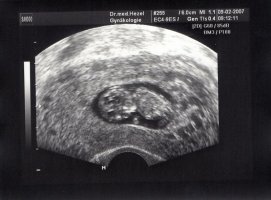

hab übrigens auch noch ein Foto von der letzten Untersuchung vor 3 Wochen (11 SSW)

• 11.SSW_1.jpg

11.SSW_1.jpg

72,9 KB · Aufrufe: 1.101

Hatte heute auch wieder eine Vorsorgeuntersuchung.Es war so cool...der kleine Muckel hat die Ärmchen hin und her bewegt.Unglaublich.

Ist jetzt 37 mm gross nach ssl gemes11. Woche! 😛reg